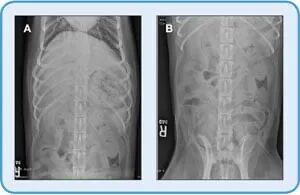

图5.背腹定位对于DV图像(B)的犬(A)的背腹(DV)定位;注意到胃内的气体在胃的底部和体部。